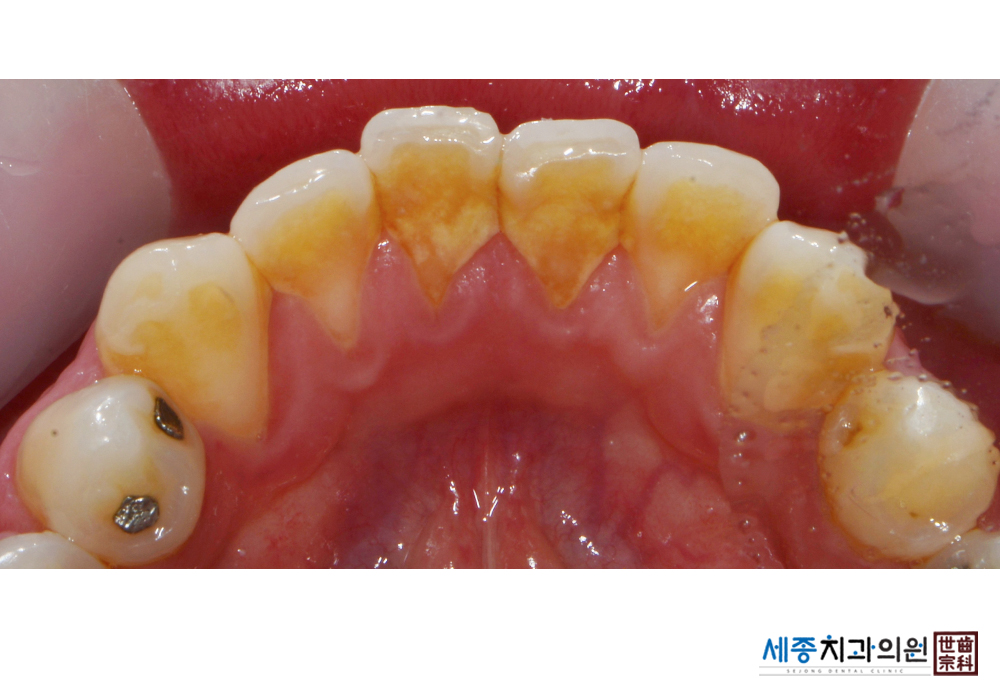

[스케일링] 치주질환 예방 스케일링 치료

치료전 : 2019-03-11

가글마취&저주파 스켈러를 사용한 스케일링